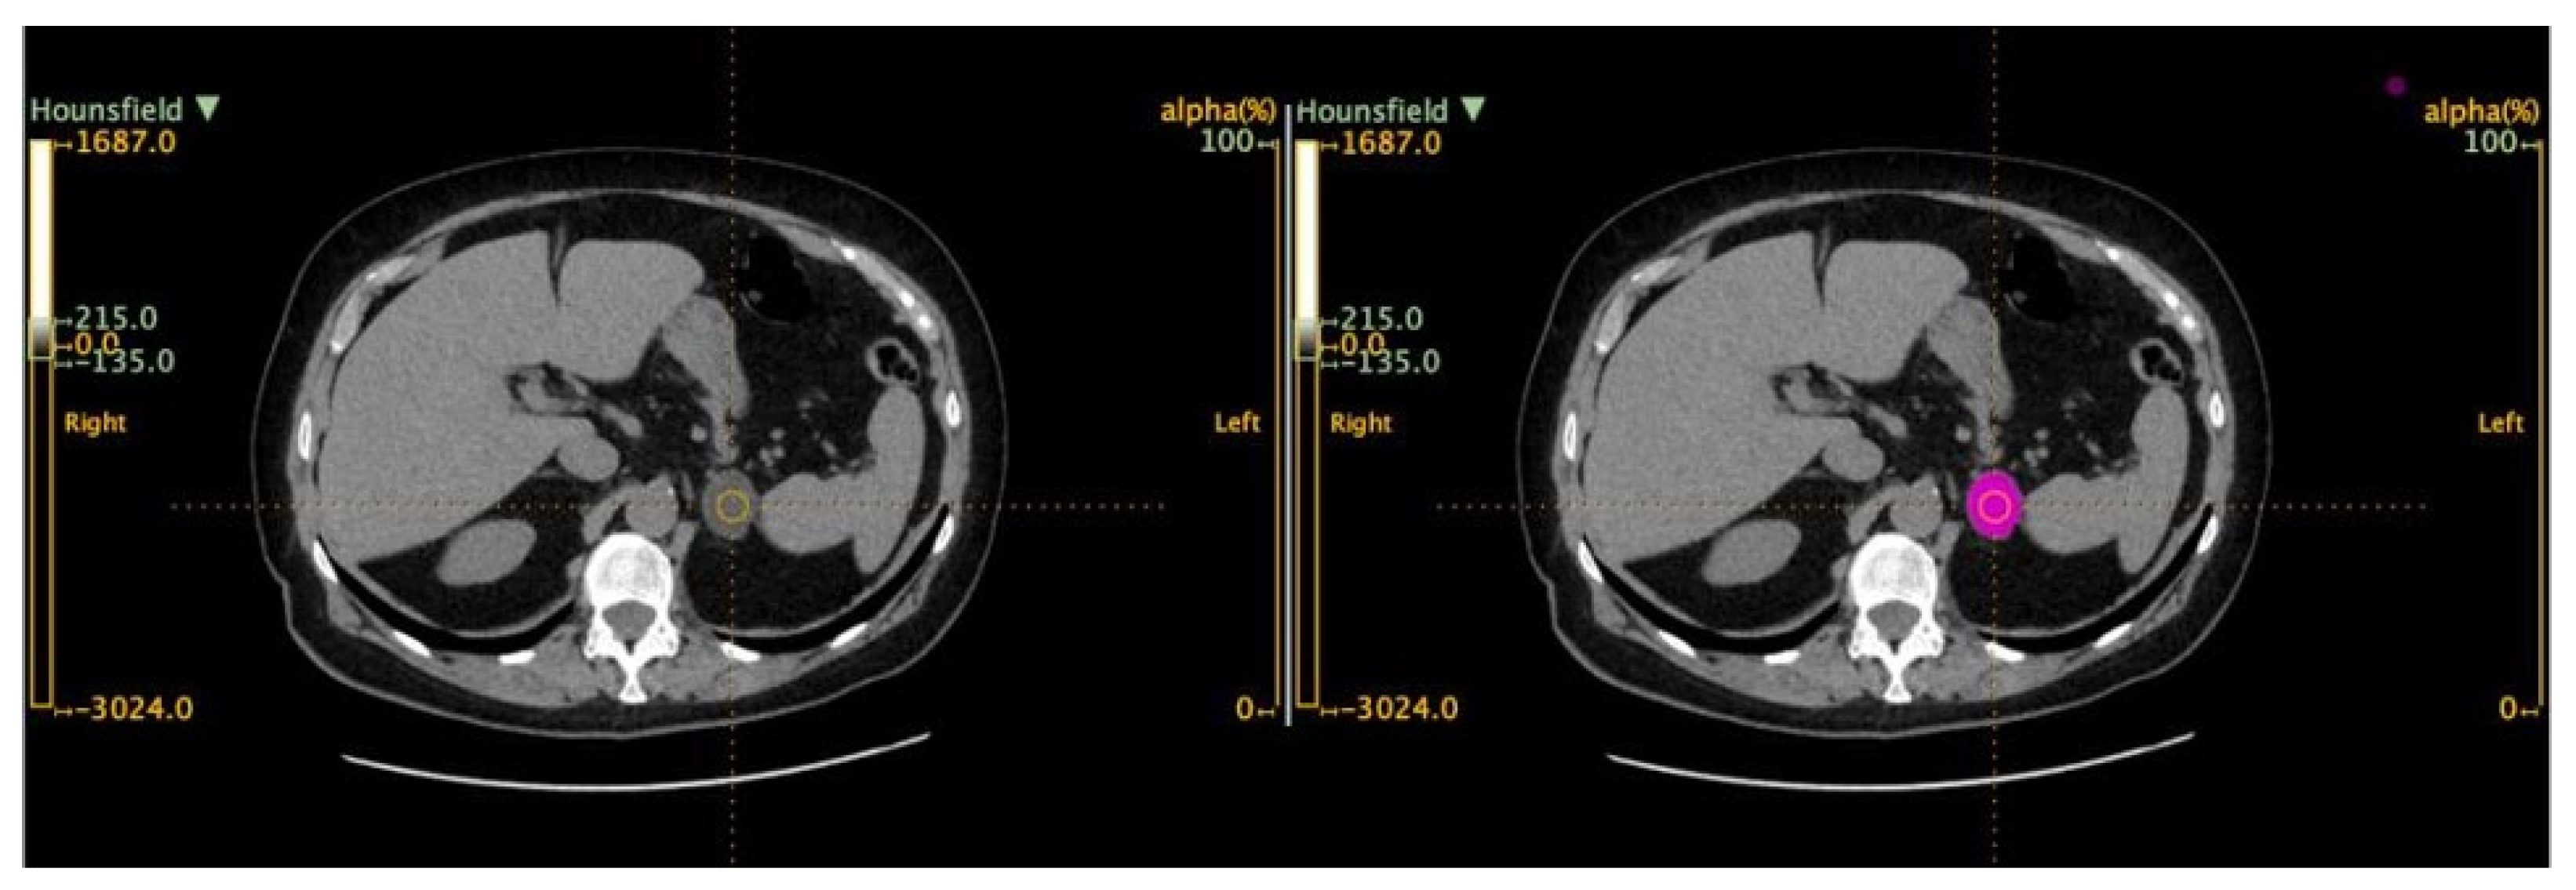

2.3. Radiomic-Based Machine Learning Modeling